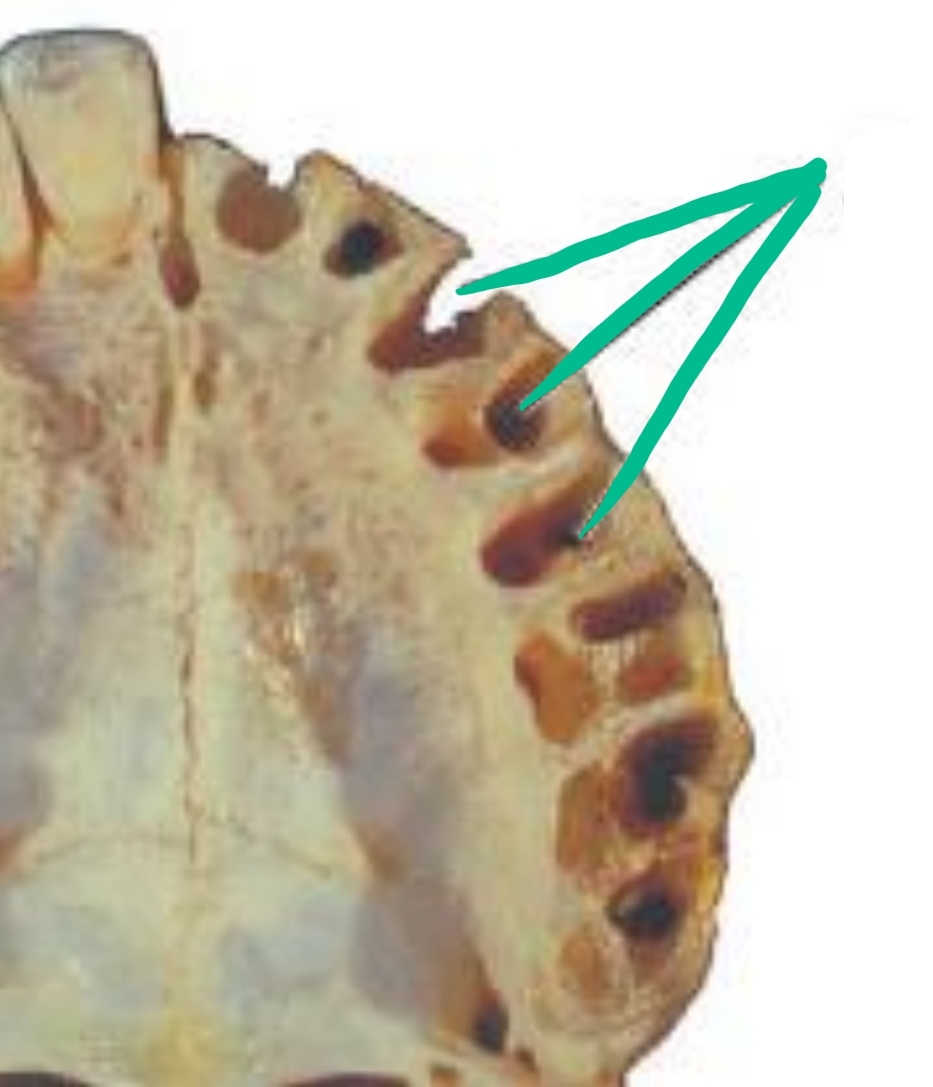

Socket (hole) where tooth is missing; where roots were

Alveolus

What two plates make up the Alveolus?

Buccal plate and Lingual plate

Outer surface of alveolus

Buccal plate

Lingual surface of alveolus

Lingual plate

located between roots

Interradicular bone

located between teeth

Interseptal bone